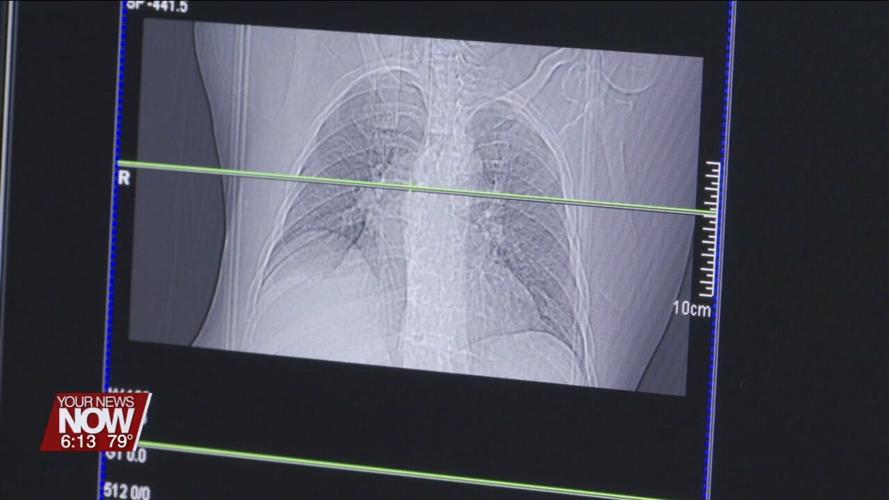

But doctors say that fear shouldn't stop a person from getting screened – especially if it can save their life. Right now, lung cancer screenings are recommended annually for adults between 50 and 80 years old who have a 20-pack-year smoking history and currently smoke, or have quit within the past 15 years. For those unfamiliar, a lung cancer screening is non-invasive and involves a CT scan which creates a detailed X-ray of the lungs. And while smoking is the leading cause of lung cancer, there can be other risk factors too. For example, lung cancer can run in a person's family or they could be exposed to something environmental like radon.

"If you are in that group that would qualify for a screening, I would certainly recommend that. So we have a chance to find any possible disease early. And by the way, most nodules or spots we find in the CT scan done for screening, they're actually benign. So often we just monitor them," commented Dr. Humberto Choi, Cleveland Clinic.